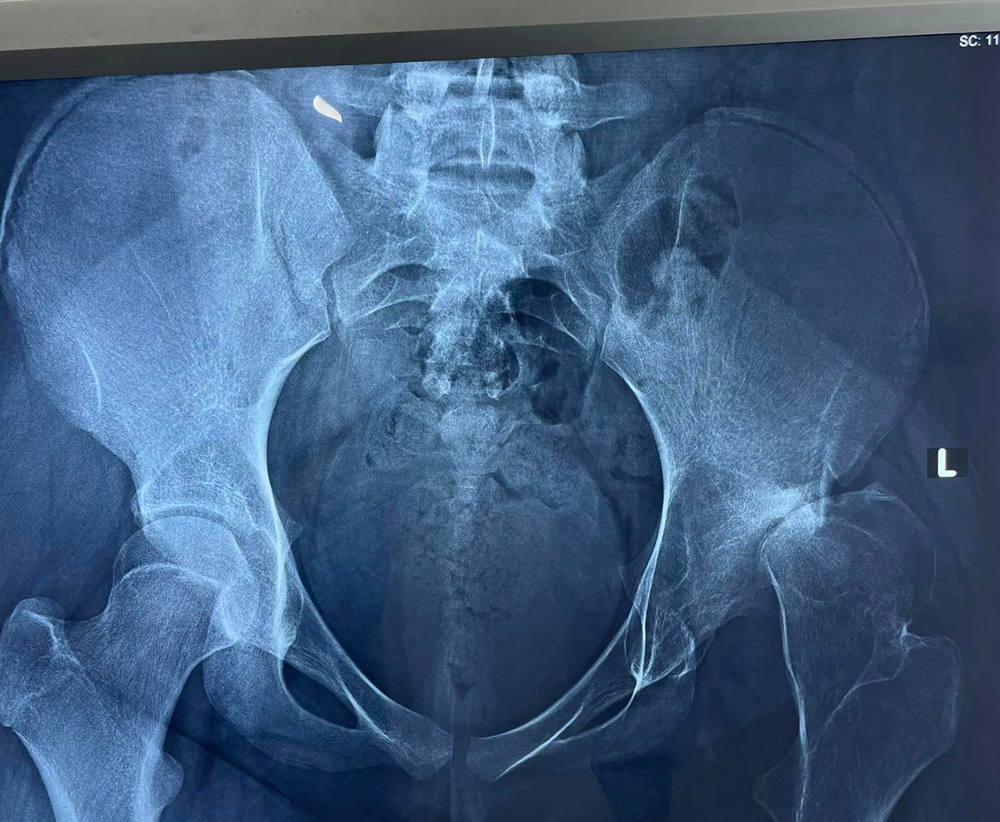

Η πολύτεκνη μητέρα, που είναι σήμερα 34 ετών, σε ηλικία μόλις 12 ετών είχε ένα άσχημο ατύχημα, όταν παίζοντας στη γειτονιά της στην Αγιάσο με άλλα παιδιά έπεσε και χτύπησε στο δεξί της ισχίο. Όταν μεταφέρθηκε στο Νοσοκομείο Μυτιλήνης υποβλήθηκε σε χειρουργική επέμβαση, η οποία, όπως αποδείχτηκε στη συνέχεια, δεν ήταν επιτυχημένη, αφού νέκρωσε η κεφαλή του ισχίου και άρχισε να κουτσαίνει. Μη έχοντας η οικογένειά της την οικονομική δυνατότητα να απευθυνθεί σε άλλους γιατρούς και εξειδικευμένα νοσοκομεία εκτός νησιού, το κορίτσι έκανε υπομονή, ελπίζοντας ότι με τα χρόνια θα επανέλθει. Όμως η κατάστασή της πήγαινε από το κακό στο χειρότερο και όπως μας είπε η ίδια το πόδι της είχε κοντύνει κατά 8 πόντους σε σχέση με το αριστερό.

Τα τελευταία χρόνια επισκέφθηκε γιατρούς σε δημόσια και ιδιωτικά νοσοκομεία της Αθήνας, αλλά κανείς δεν αναλάμβανε την περίπτωσή της, υποστηρίζοντας ότι είναι πολύ δύσκολη έως αδύνατη η επανόρθωση της ζημιάς που έχει υποστεί στο ισχίο κατά το πρώτο χειρουργείο. Εν τω μεταξύ, η ίδια αντιμετώπισε σε ηλικία 17 ετών κι άλλο σοβαρό πρόβλημα υγείας, αυτή την φορά στο κεφάλι, όταν μετά από έντονους πόνους απευθύνθηκε στο Βοστάνειο για εξετάσεις κι εκεί διαπιστώθηκε ότι είχε ανεύρυσμα. Οι γιατροί φρόντισαν για την άμεση μεταφορά της στην Αθήνα και στο Νοσοκομείο “Γεώργιος Γεννηματάς”, όπου υποβλήθηκε σε διαδοχικούς εμβολισμούς για να αντιμετωπίσει κι αυτό το πρόβλημα. Έκτοτε όμως, υπέστησαν ζημιά τα νεύρα και τα αγγεία του δεξί της χεριού με συνέπεια να μην είναι πλέον λειτουργικό και να είναι μονίμως μουδιασμένο.

Η επέμβαση ολικής αρθροπλαστικής ισχίου έγινε στις 20 Ιουνίου, στο Νοσοκομείο “General Hospital”, στην Αθήνα, από τον γνωστό ορθοπεδικό, Βασίλη Καϊλή. Όλα πήγαν καλά και η 34χρονη επέστρεψε την Δευτέρα στο σπίτι της και έχει ξεκινήσει ήδη τις φυσικοθεραπείες. Όπως μας είπε «είμαι τόσο χαρούμενη και ευτυχισμένη που όλα πήγαν καλά, γύρισα στο σπίτι μου και στα παιδιά μου και ξέρω ότι σε λίγο καιρό θα μπορώ να φροντίζω την οικογένειά μου και να περπατάω χωρίς πόνους μετά από τόσα χρόνια. Θέλω να πάω με τα πόδια στον Ταξιάρχη, όπως πήγαινα παλιότερα και ο γιατρός μου είπε ότι σε λίγους μήνες θα γίνει κι αυτό. Ευχαριστώ μέσα από την καρδιά μου τον κ. Καϊλή, την Διαμάντω Ρουγκέλλη, την οικογένειά μου και όλους τους συγχωριανούς μου που με βοήθησαν και εύχομαι υγεία σε όλο τον κόσμο».

Η συγκεκριμένη επέμβαση είναι ένα από τα πιο δύσκολα χειρουργικά περιστατικά που μπορεί να αντιμετωπίσει στην καριέρα του ένας ορθοπεδικός χειρουργός και όπως είπε ο Β. Καϊλής, αντιμετωπίστηκε με απόλυτη επιτυχία. «Η 34χρονη με χρόνιο εξάρθρημα ισχίου (μετατραυματικό) και οστεοαρθρίτιδα σοβαρού βαθμού, στην οποία πραγματοποιήθηκε ολική αρθροπλαστική ήταν ένα μικρό θαύμα που κάνει αυτή τη μέρα σίγουρα πολύ σημαντική και αξέχαστη στην καριέρα μου», ανέφερε ο ίδιος.